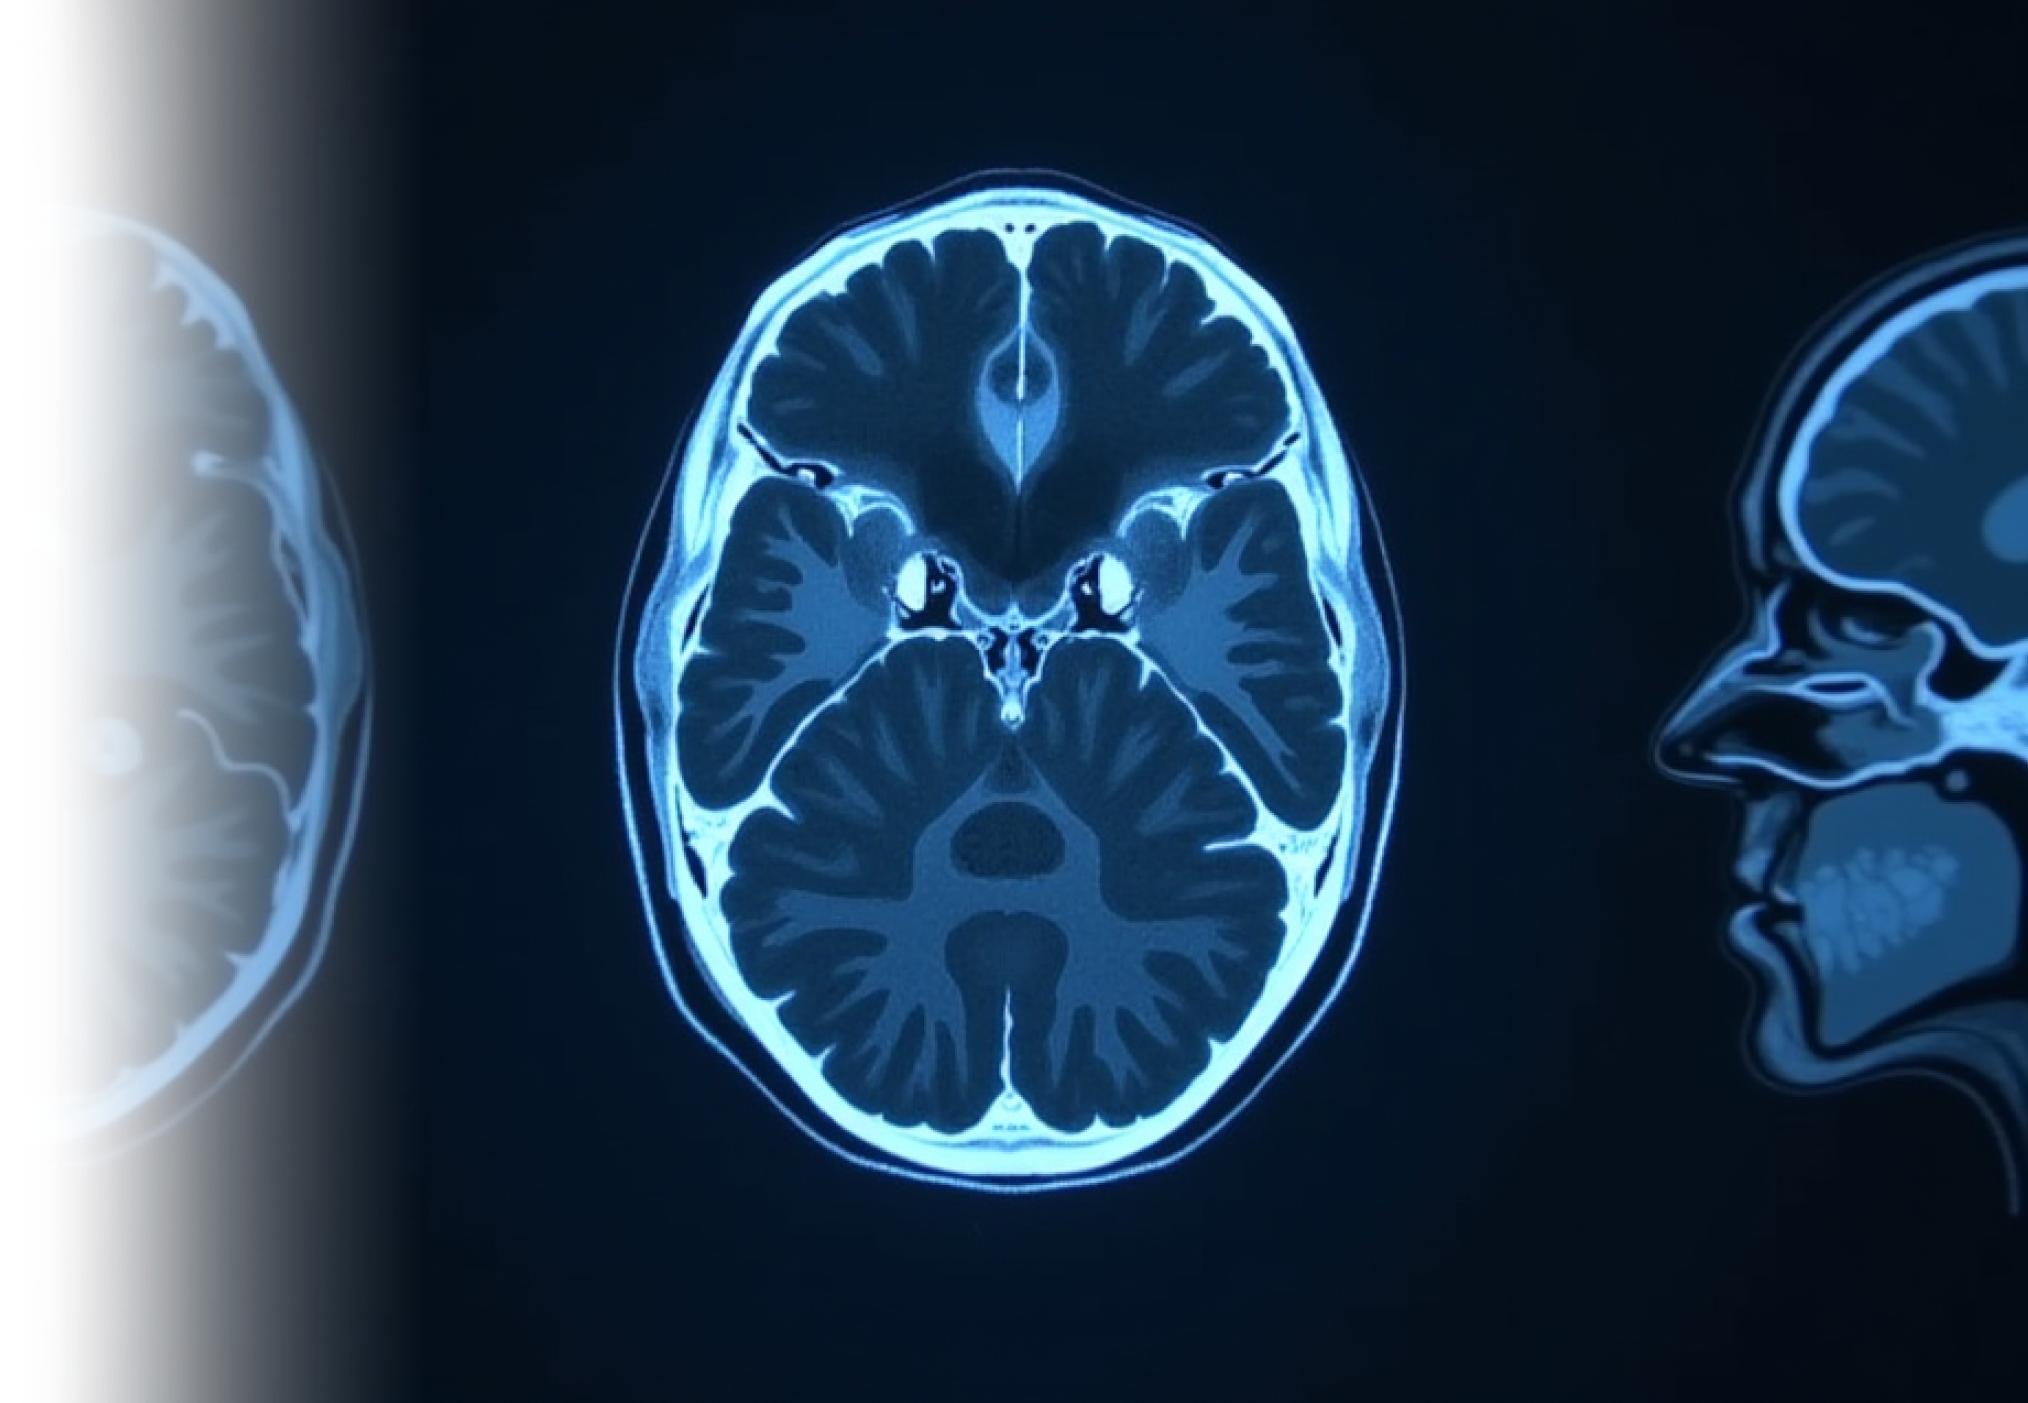

Компьютерная томография головного мозга – важный метод исследование, которое позволяет получить детальное представление о состоянии головного мозга.

КТ позволяет оценить вещество мозга на наличие ишемических изменений, образований вещества мозга, внутримозговых и оболочечных гематом, а также анатомию мозга.